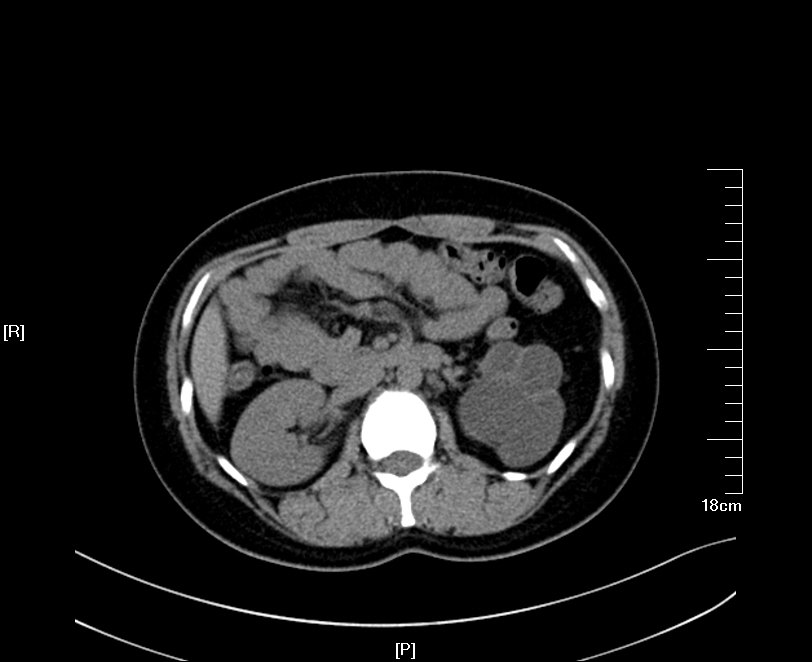

2016年04月手术患者,男性,37岁,盐城人,十七年前曾因左输尿管结石引起肾绞痛在当地予以多次震波碎石,疼痛缓解后未于重视,其间未予复查,一直于当地务农,自称今年来苏打工,招工体检时发现左肾重度积水一周来院求诊;CT:左侧肾脏重度积水,皮质菲薄,左侧输尿管结石约1.5cm,GFR:左侧4.89ml/min,右侧56.9ml/min。因右侧健肾代偿,肾功能正常:Cr 98umol/L;术前诊断:左输尿管结石 左肾重度积水 左肾无功能,鉴于左输尿管结石梗阻时间太长,左肾已几乎无功能,呈现皮囊肾样改变,最终只能行腹腔镜下左侧肾输尿管切除术,一并取出皮囊肾和输尿管及结石。

增强CT检查提示:左侧肾脏重度积水 皮质菲薄,几乎已无功能

左侧输尿管结石约1.5cm

GFR:左侧仅4.89ml/min,与增强CT检查相符